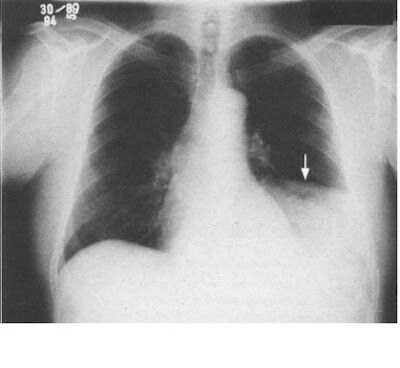

O que é sinal da silhueta? Quais são as causas? Perda da definição de uma estrutura, associada a consolidações ou massas. Pneumonia, derrame pleural e neoplasias.

Que sinal é esse? Sinal da silhueta